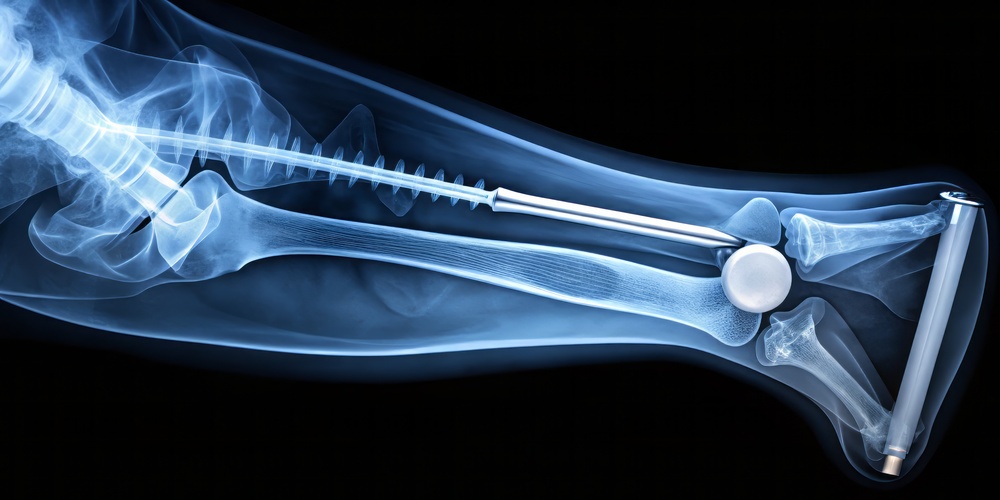

A fixação intramedular é o padrão-ouro para fraturas diafisárias do fêmur e tíbia, com altas taxas de sucesso. No entanto, uma parcela dos pacientes enfrenta o desafio da consolidação atrasada ou da não união. Entre as opções de tratamento, a dinamização – que consiste na remoção seletiva de parafusos de bloqueio para permitir compressão axial no foco da fratura – é minimamente invasiva, mas sua eficácia relatada na literatura é bastante variável.